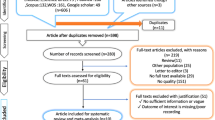

The master search resulted in 307 articles, from which 55 duplicates were removed (Fig. 1). After screening the remaining 252 articles, 234 articles were excluded (e.g., non-original papers and case reports, cf. Fig. 1), and 18 studies were assessed by full text. Two articles turned out to be reviews, five were abstracts, one paper employed stand-alone PET only, and these eight studies were excluded. Thus, ten eligible studies met the inclusion criteria. However, one of these was not sufficiently transparent: From the data provided in the article, it was not possible to determine the number of true positive, true negative, false positive, and false negative findings and it was not possible to follow their results. Therefore, this article was excluded due to the failure of data extraction [19].

Adapted from: Moher D, Liberati A, Tetzlaff J, Altman DG, The PRISMA Group (2009). Preferred Reporting Items for Systematic Reviews and Meta-Analyses: The PRISMA Statement. PLoS Med 6(6): e1000097. https://doi.org/10.1371/journal.pmed1000097

PRISMA flow chart for literature selection